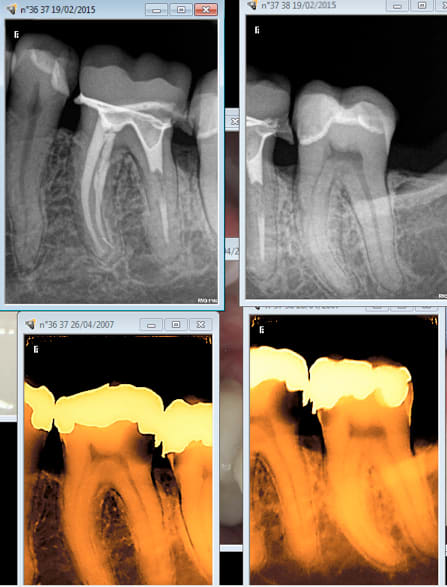

Remarque ca tient dans le temps à 9 ans ....

Tu me diras la ceram sur 25 du protho est bien pourrie aussi. -)

Aie 9 ans aussi. Ouh lalalala la cata. J'aurais du faire des radios après la pose il y a un binz en distal de la 36. -)))